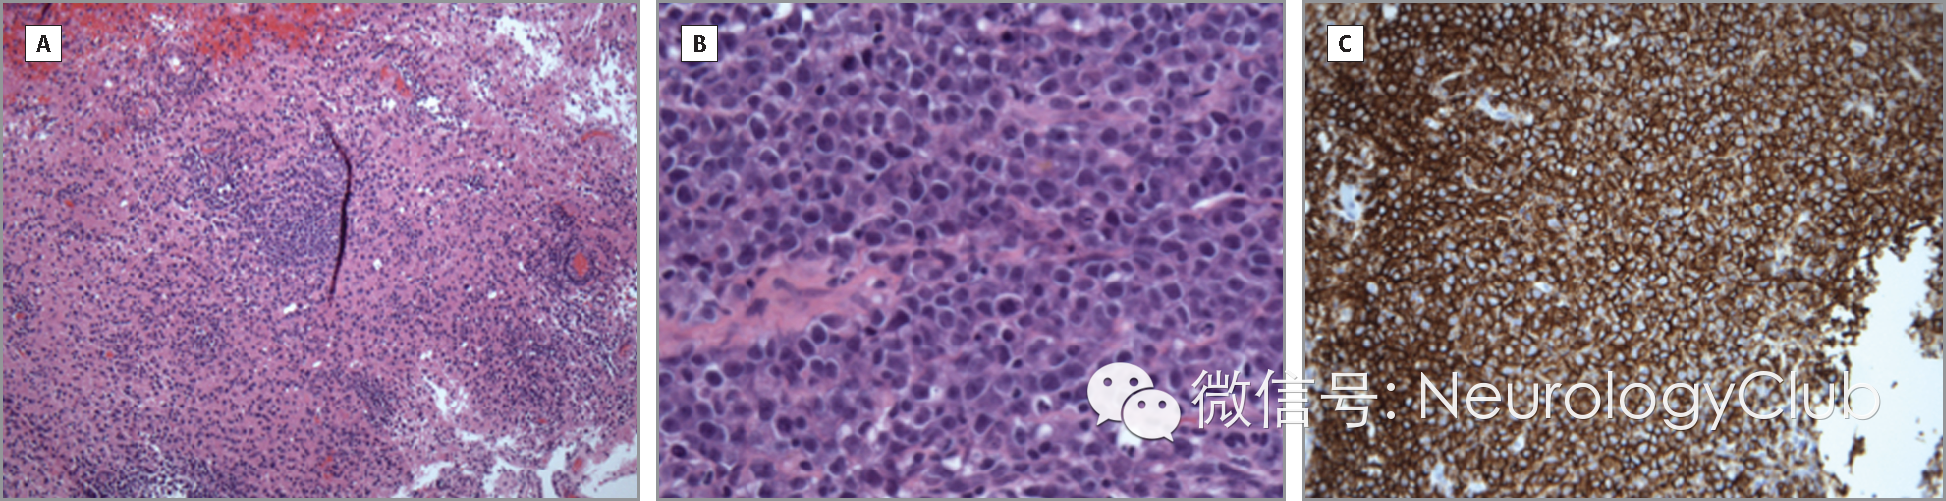

患者脑脊液细胞学检查发现淋巴瘤细胞。最终立体定向活检明确诊断。患者接受以静脉注射大剂量甲氨蝶呤为基础的治疗后,临床症状与影像学异常迅速改善。

(A:HE×10;B:HE×40;C:CD20染色阳性)

原发性中枢神经系统淋巴瘤